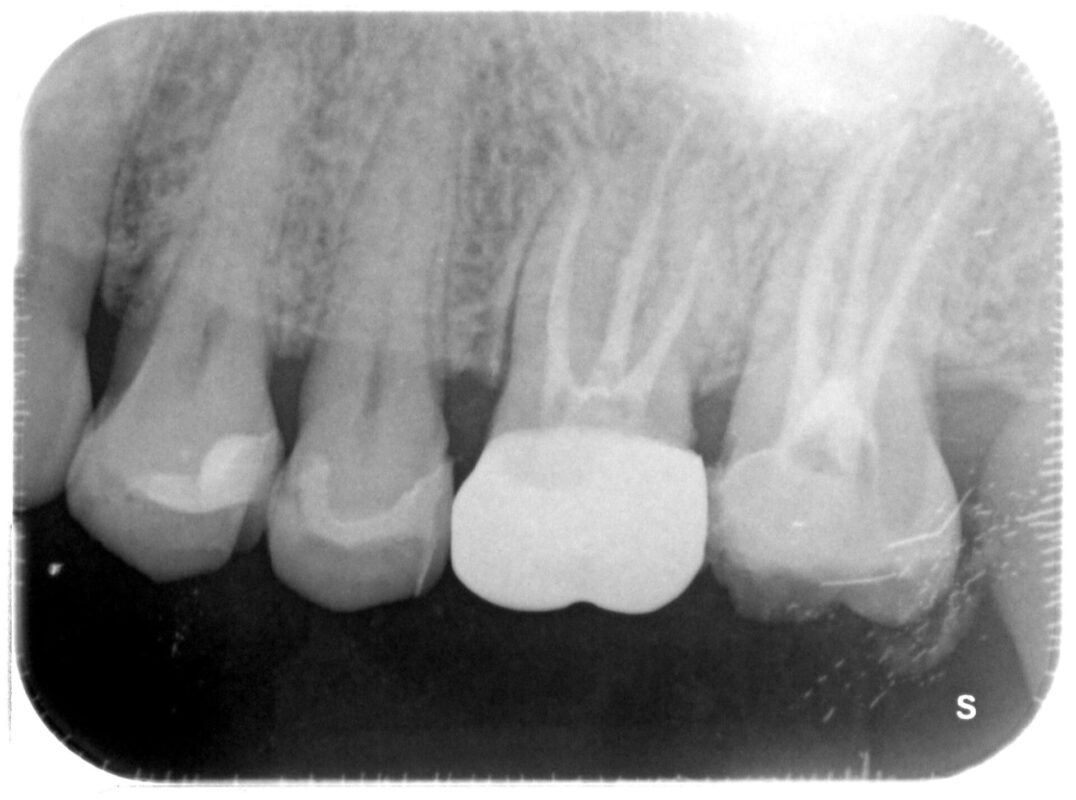

術前

┗7(写真右端)冷たいものが強くしみると他院受診したものの、知覚過敏と言われたものの、段々痛

みも出てきて当院受診されました。

当院でレントゲン写真撮影したところ、金属の下に明らかな影が。

金属除去したところ非常に深い虫歯があり、根管治療必要となりました。